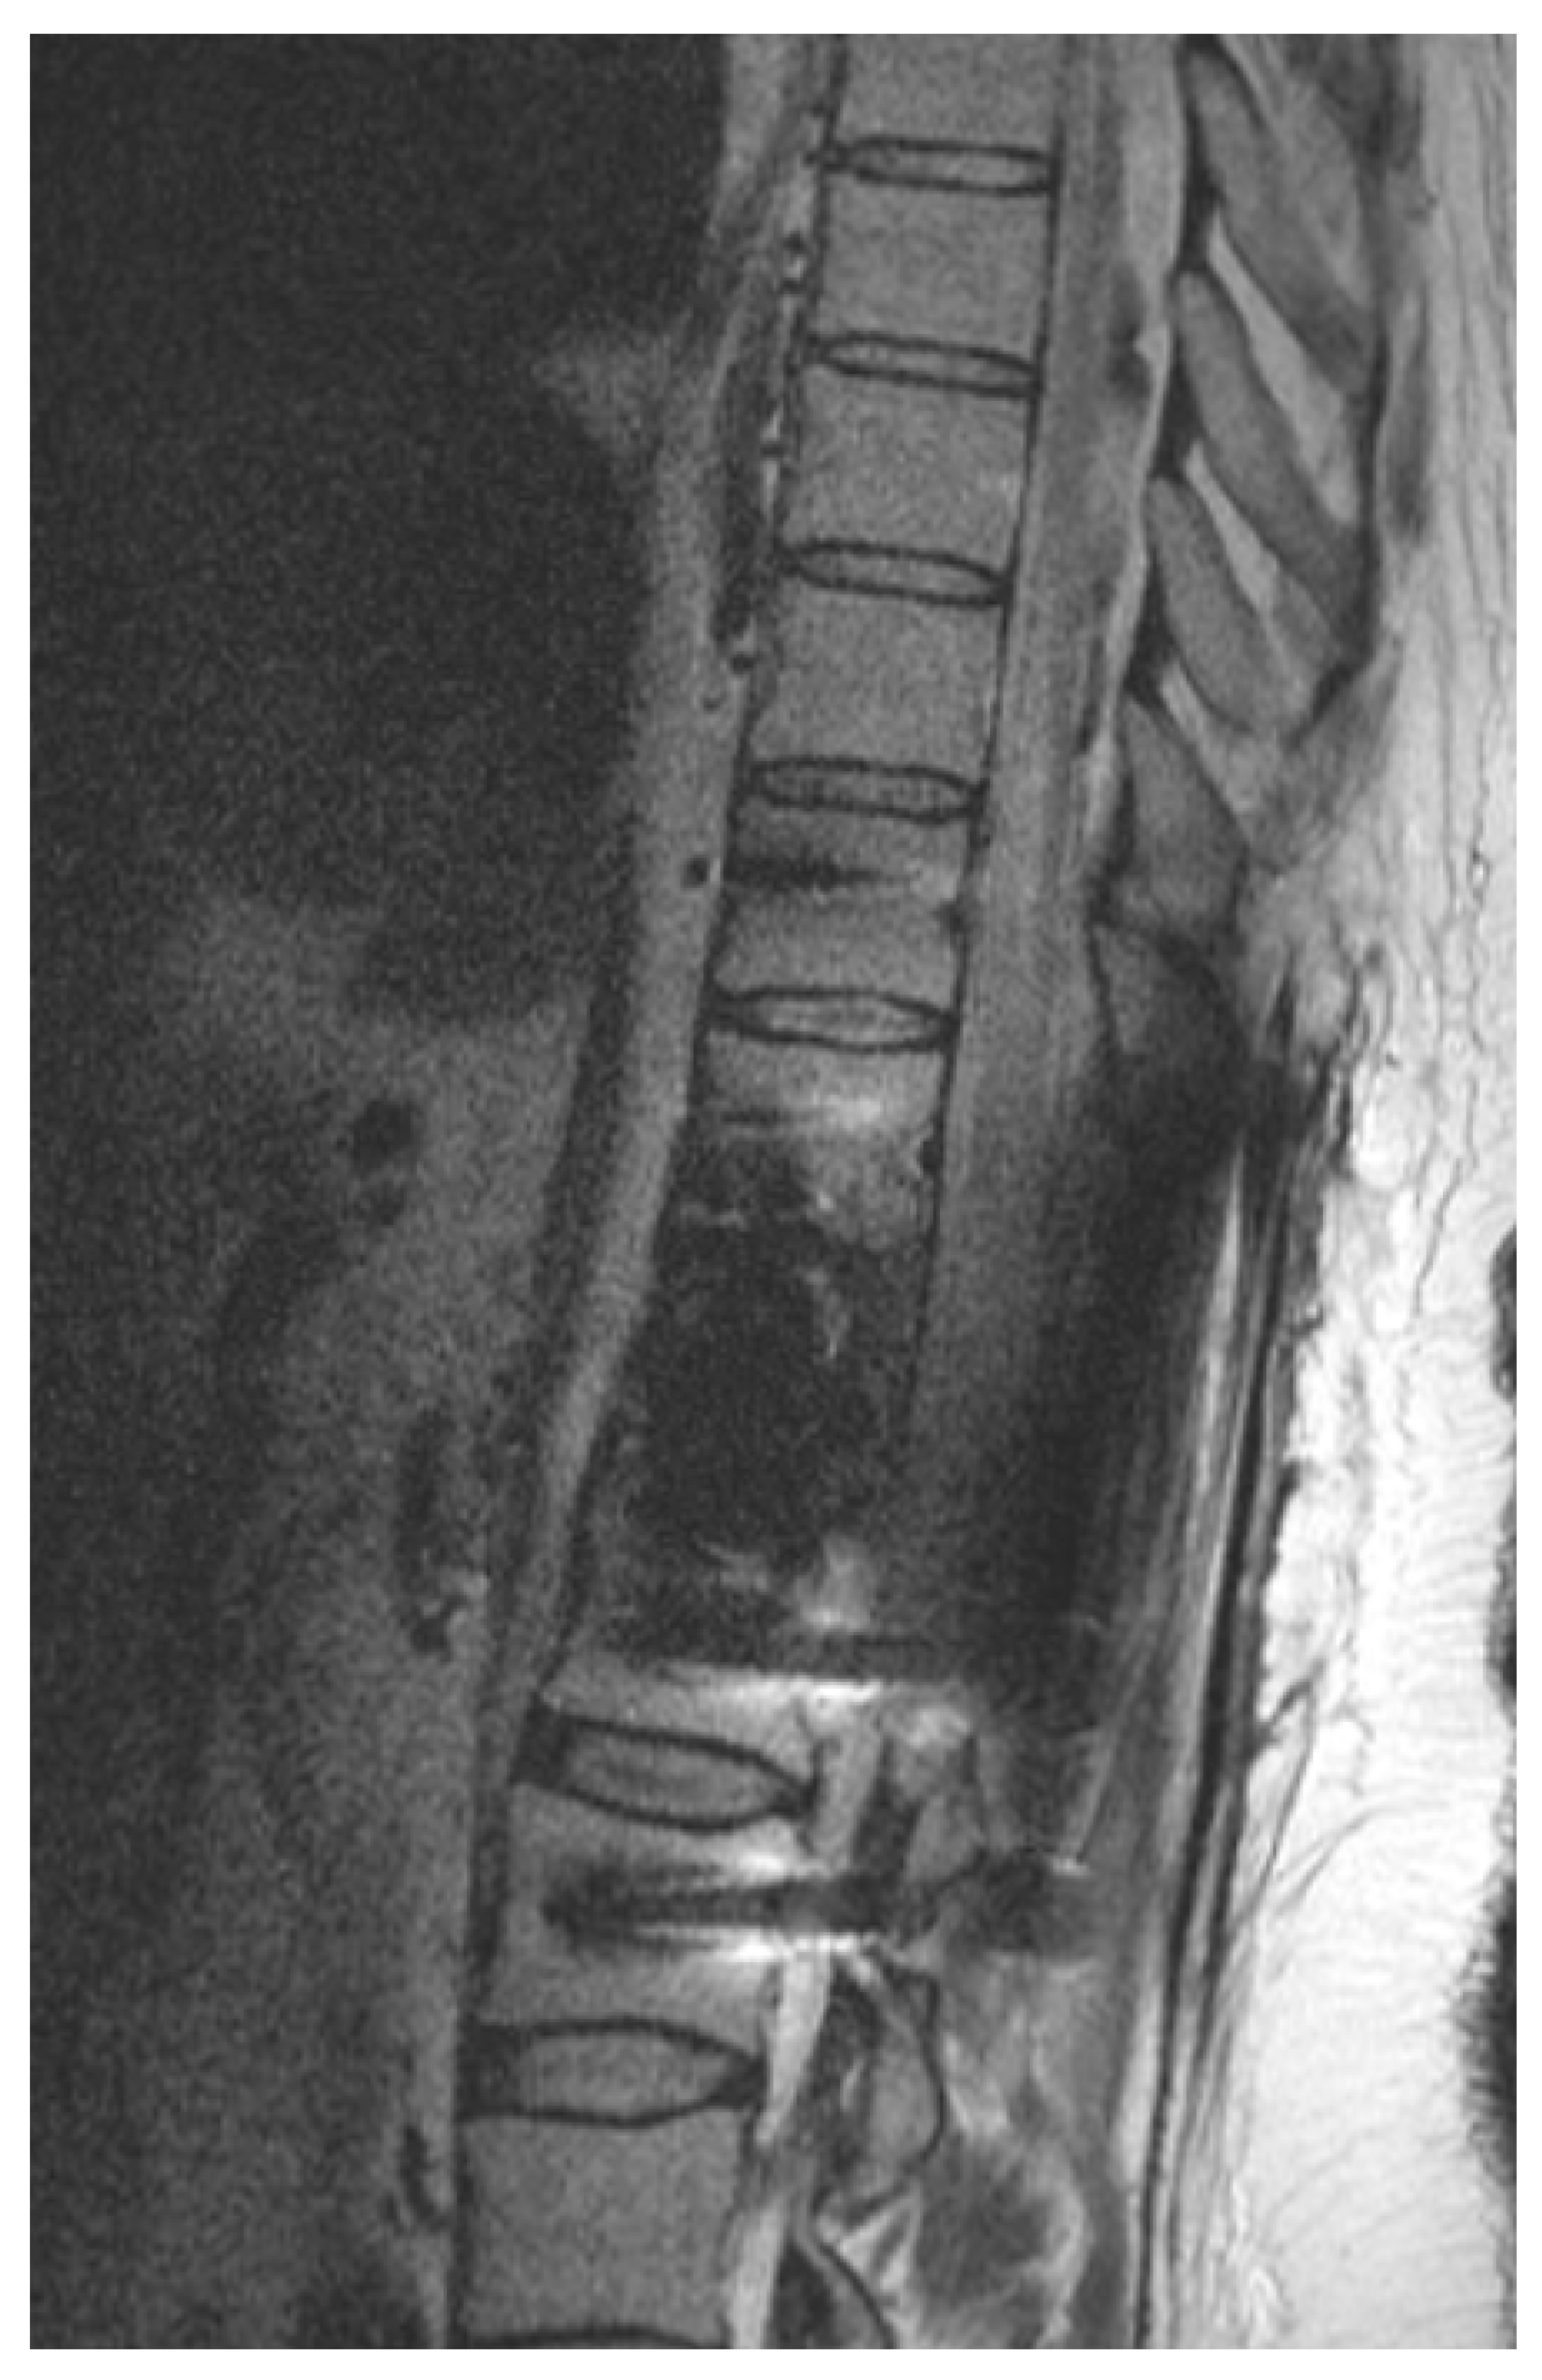

Figure 2.

Illustrative example of postoperative imaging. Postoperative 1.5 T MRI after CFR-PEEK instrumentation and resection of renal cell carcinoma metastasis that was embolized preoperatively. Patient showed paraplegia postoperatively. Because of reduced artifacts, MRI could rule out epidural hematoma and depicted spinal cord edema caused by ischemia.